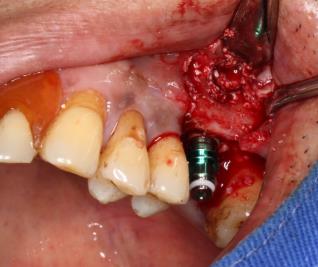

口腔检查 :全口咬合关系基本正常。26缺失,缺失区牙槽骨丰满度良好,颊舌向宽度约9mm。牙龈状况良好,无溃疡红肿。缺牙区邻牙未见明显倾斜,合龈高度约6mm。 CBCT显示:26缺失,骨质III类,缺牙区牙槽嵴宽度约9mm,牙槽嵴距离上颌窦底为6-7mm,窦嵴距不足。

诊断:26牙缺失;  治疗:26牙行种植修复(经牙槽嵴上颌窦提升术)  治疗方式:术区行利多卡因+布比卡因阻滞麻醉,碧兰麻行浸润麻醉。常规消毒铺单,待麻药显效后,于26牙槽嵴顶做近远中切口,剥离术区黏骨膜,26远中做颊侧附加切口,显露术野。生理盐水冲洗冷却下大球钻修整骨面,小球钻确定26种植位点。先锋钻确定种植体植入方向,扩孔钻逐级扩大种植窝洞,窝洞预备至接近上颌窦底,插入深度测量尺观测深度与方向,扩孔钻扩大种植窝洞。使用上颌窦底冲压骨凿,轻敲骨凿底部至10mm,做鼻腔鼓气试验,检查上颌窦黏膜完整性,最终植入种植体,查种植体方向和初期稳定性良好,旋入覆盖螺丝。严密缝合创口。常规止血,术毕。